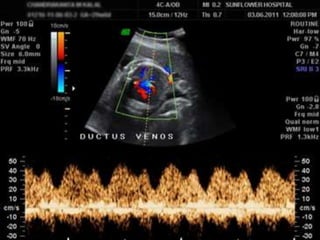

Ultrasound imaging and insonation

• A Sagittal anterior insonation offers the best

visualization of the Ductus venosus .

• An oblique transverse section may be more

convenient and easier to obtain in some fetal

position but rarely offers visualization of the

entire length of the vessel.

• Color Doppler is an indispensable tool to

identify the high velocity flow at the isthmus

of the ductus venosus.

• Pulsed wave Doppler can be obtained in both

Sagittal and transverse view and no angle of

correction is usually needed.

• The sample volume should be kept as wide as

the geometric detail of the vessel to reduce

interference by surrounding vessels